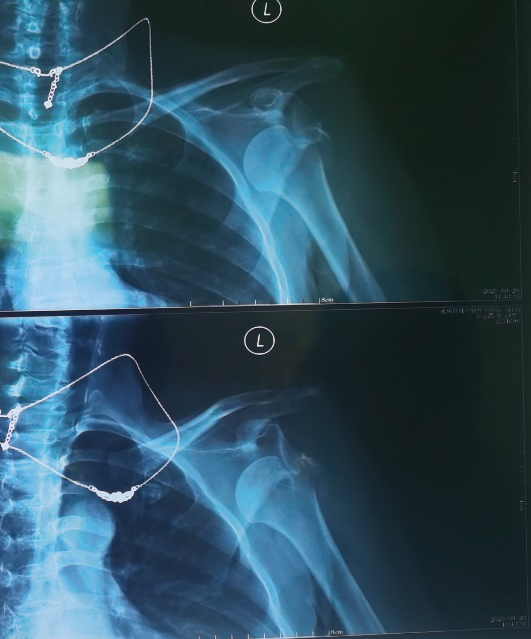

患者术前X线检查可见肩关节脱位及肱骨大结节骨折